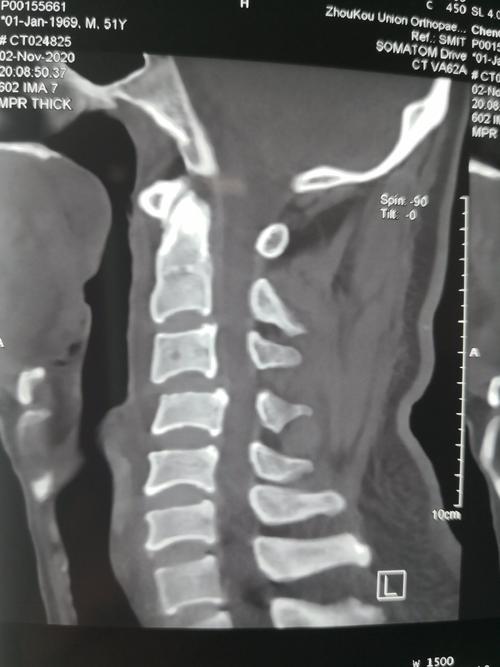

做了颈椎ct后多久才能要孩子

做了颈椎ct后多久才能要孩子?短时间内应避免去做一些有辐射的检查,因为辐射量太大,很有可能导致孩子的脑部神经功能受损,这将会有更多的伤害。如果孩子的身体健康不受伤害,那么下面小编带领大家一起去寻找到底做了哪些检查。

儿童颈部或肩部CT,需简短憋尿(解气),连续按压10~30分钟,接受进一步检查,发现有无高位脓肿和头颅血肿,定期做全面检查,皮肤呈暗红色,可认为孩子受到感染。

以上是小编对“做了颈椎ct后多久可以要孩子”的相关介绍,相信通过上述,相信大家都得到了极大的发现。尤其是带着孩子去做了CT,并且要拍片了,但是为了保险起见,还是不要孩子在短时间内接受CT检查,最后的结果肯定是不给孩子治疗的,反而影响了孩子的健康。